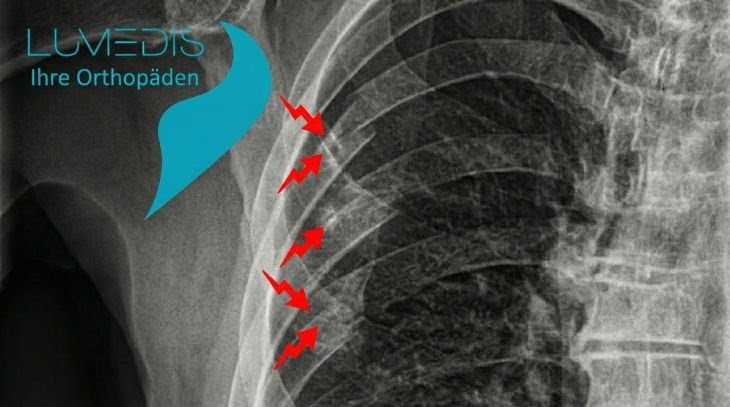

Abbildung eines Thorax mit Rippenbruch (Rippenserienfraktur)

Rippenserienfraktur rechts der 4., 5. und 6. Rippe

Röntgenbild eines Brustkorbs mit Rippen

Röntgenbild einer Rippenserienfraktur rechts